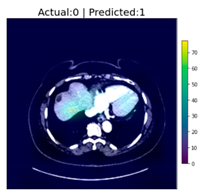

After reaching an accuracy of 95.89%, the training was stopped, and the Grad-CAM method was applied for each of the test images, including those that were falsely classified. The following figure, Figure 6, shows some of the CT images with their associated heat-maps overlaid. In the legends of the figures, “Actual” shows the label for DeepLesion, and “Predicted” shows the output of the CNN classifier.

Figure 6.

CT images with Grad-CAM-generated heat-maps overlaid.

There is a single case among the 16 images, image 15, where the CNN classifier mis-classified. The image contained no tumor, as DeepLesion labeled and was verified by the clinician, but the classifier generated a false positive. The clinician further clarified that the image did contain cyst(s), but not a tumor, which may be the reason for the false classification. The false prediction may be an indication that the classifier was not trained sufficiently to differentiate between cysts and tumors, as the DeepLesion database did not label cysts. However, the Grad-CAM heat-map was somewhat helpful by pointing out the region(s) where the classifier thought tumors may exist.